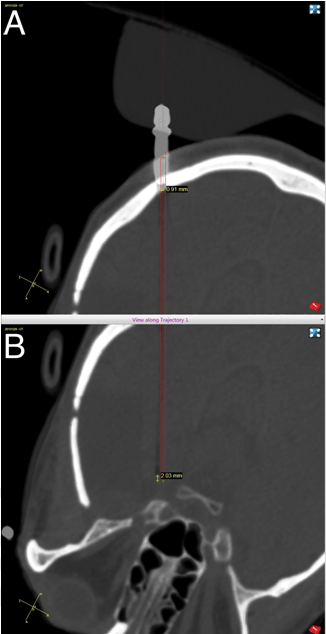

The patient underwent a preoperative volumetric MRI for stereotactic navigational purposes. The patient was placed under general anesthesia and then placed in a lateral position. We used the ROSA robot (MedTech Surgical, Inc, Montpellier France) to assist with implantation of a laser cannula through a transoccipital approach to the mesial temporal lobe. The patient was placed in a Leksell stereotactic head frame (Elekta, Crawley, United Kingdom) to connect him to the robot (i.e., not for stereotactic navigational purposes). Additionally, bone fiducials were used because facial registration is less accurate when the patient is in the lateral position. A mesial temporal trajectory was planned with the ROSA navigation software, including the entry point and trajectory needed to reach the target (Figure 1). A percutaneous burr hole was made on the scalp at the entry point and a PMT skull bolt (PMT Corporation, Chanhassen, Minnesota) was placed in the correct trajectory. We passed a cannula through the skull bolt and advanced it to the predetermined depth (Figure 2). The laser applicator was then placed within the cannula and secured. The patient was then transported to the MRI suite for the remainder of the procedure. Imaging confirmed correct placement of the laser applicator and then the LITT commenced.

Figure 1: Panel A-ROSA display demonstrating planned and actual (A) Entry point, and (B) Target.